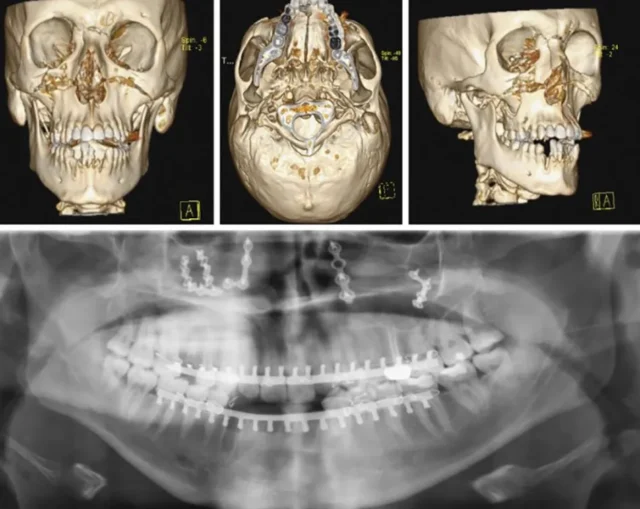

- Chẩn đoán hình ảnh: Sử dụng CT-Scan 3D (Cone Beam CT) để đánh giá chính xác vị trí, mức độ gãy và số lượng mảnh gãy của xương hàm mặt (xương hàm trên, hàm dưới, gò má, sàn hốc mắt). Việc này cực kỳ quan trọng đối với chấn thương đa tầng.

- Nắn chỉnh và cố định xương: Các mảnh xương gãy (xương hàm trên, xương gò má, xương hàm dưới…) sẽ được nắn chỉnh về đúng vị trí giải phẫu. Sau đó, chúng được cố định vĩnh viễn bằng hệ thống nẹp và vít titan y tế. Vật liệu titan có tính tương hợp sinh học cao, đảm bảo xương lành vững và không bị thải ghép.